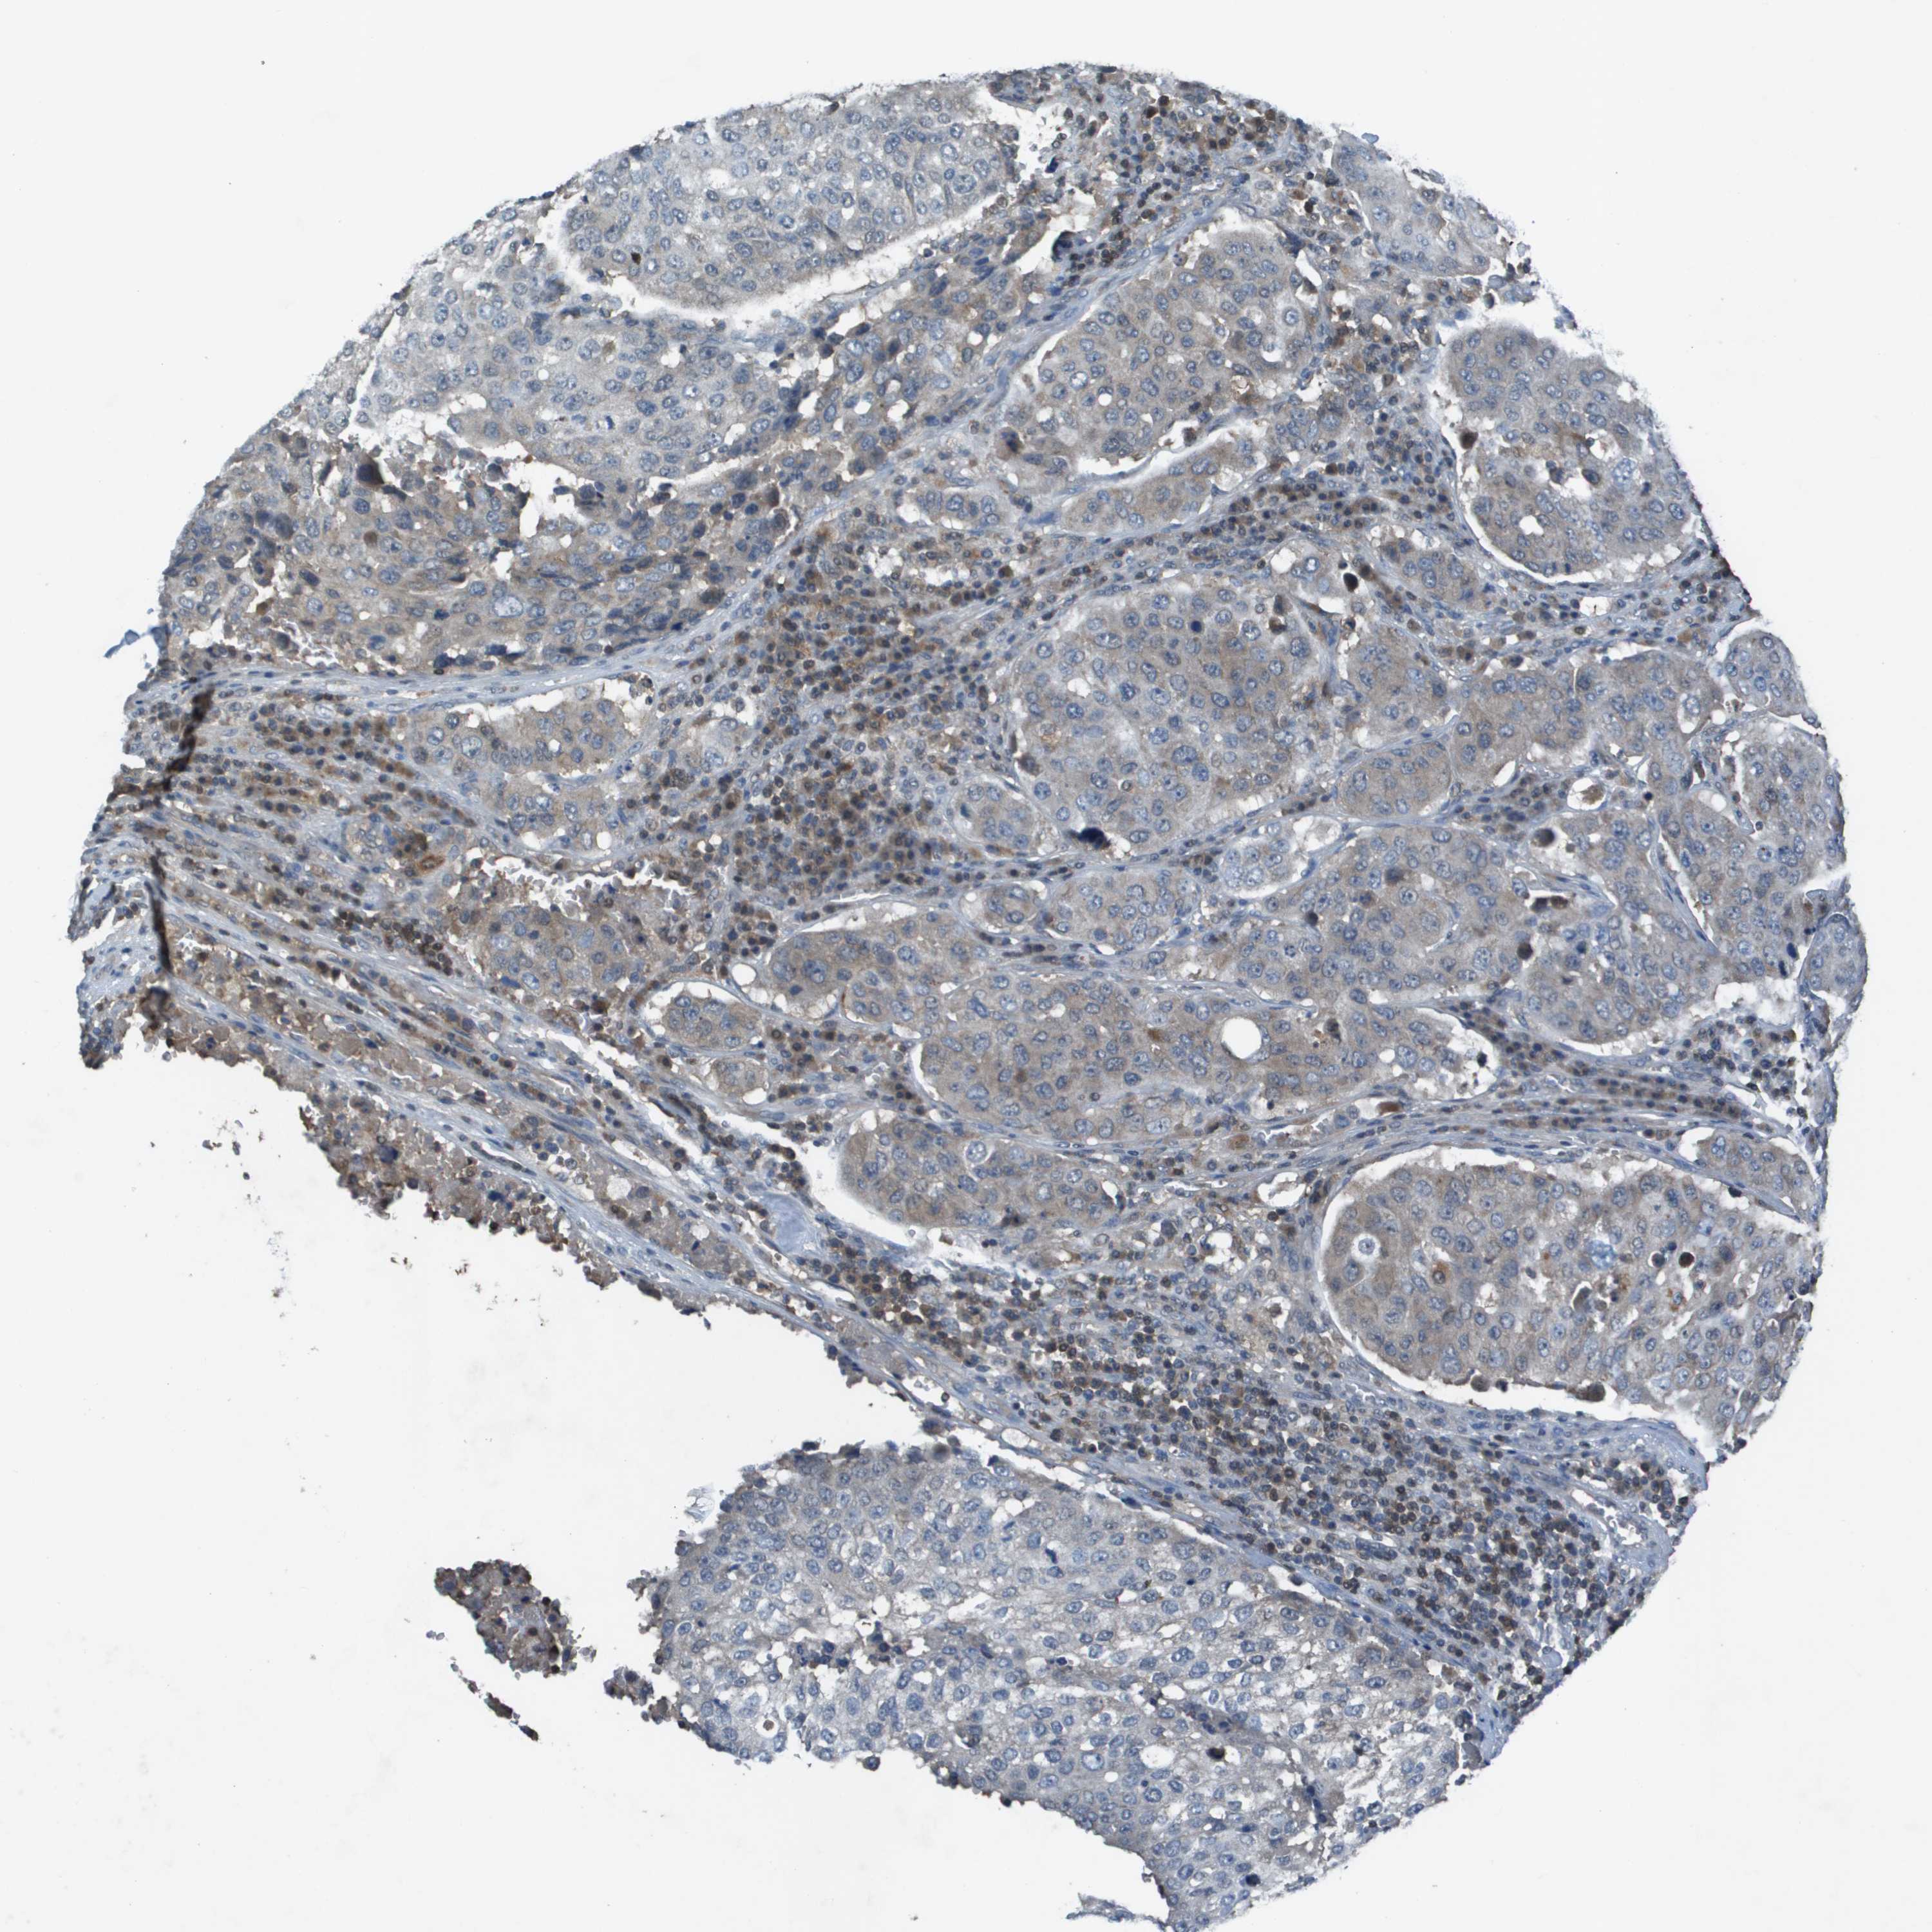

UROTHELIAL CANCER - Protein expressioni

A mouse-over function shows sample information and annotation data. Click on an image to view it in a full screen mode. Samples can be filtered based on level of antibody staining by selecting one or several of the following categories: high, medium, low and not detected. The assay and annotation is described here.

Note that samples used for immunohistochemistry by the Human Protein Atlas do not correspond to samples in the TCGA dataset.

Antibody stainingi

Antibody staining in the annotated cell types in the current human tissue is reported as not detected, low, medium, or high, based on conventional immunohistochemistry profiling in selected tissues. This score is based on the combination of the staining intensity and fraction of stained cells.

Each image is clickable and will lead to virtual microscopy that enables deeper exploration of all samples and also displays staining intensity scores, fraction scores and subcellular localization as well as patient and tissue information for each sample.

Antibody HPA011753

Antibody HPA017206

Antibody CAB004347

Staining

High

Medium

Low

Not detected

Intensity

Strong

Moderate

Weak

Negative

Quantity

>75%

75%-25%

<25%

None

Location

Nuclear

Cytoplasmic/membranous

Cytoplasmic/membranous,nuclear

Urothelial carcinoma, Low grade

Urothelial carcinoma, High grade